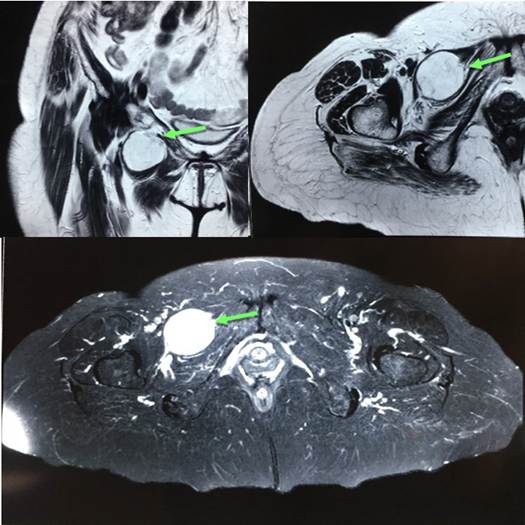

La tomografía computarizada (TC) de pelvis es el estándar dorado para el diagnóstico de esta entidad, porque su sensibilidad puede ser mayor al 90 % 4,25 y es capaz de mostrar hernias bilaterales asintomáticas. Fue sugerida desde 1983 por Cubillos, y su imagen típica es una burbuja con un nivel hidroaéreo, localizada entre el músculo obturador externo y el pectíneo (Figura 5) o entre ambos músculos obturadores (hernia obturatriz tipo 3 o intermembranosa). En otras ocasiones, esta imagen representa el segmento de asa intestinal con el saco herniario protruyendo entre los músculos pectíneo y obturador externo en el tipo I 7,10,17,26-28.

Por último, debido a su superior resolución tisular, la resonancia magnética nuclear (RMN) muestra mayor valor diagnóstico en la identificación de hernias tipo I y sensibilidad similar a la TC en el tipo II y III, sin embargo, su disponibilidad en el ámbito de urgencia tiende a ser limitada o retardada, por lo que no es mejor opción que la TC 17. Con imágenes coronales y axiales T2 y axial STIR (secuencia empleada que permite suprimir la señal de determinados elementos o tejidos específicos, como grasa o agua), se muestra el saco herniario distendido por líquido entre los músculos pectíneo y obturador externo (Figura 6).